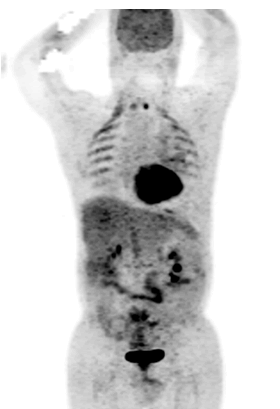

PET–CT with 18F-FDG was performed showing physiological uptake of 18F-FDG in the 3D Maximum Intensity Projection (3D MIP) (Figure 1), and unhabitual diffuse and stepped hypermetabolism interesting intercostals muscles and diaphragm in (3D MIP) and Fused PET/CT images in axial sections (Figure 2), this exceptional uptake was explained by the breathing difficulties relating to dyspnea. In addition to this finding, multiples pleural, pericardial and abdominal effusions without hypermetabolism, were observed in the context of hydrops. We report in our exploration the total disappearance of the pathological lymph nodes hypermetabolism previously described in the intermediary PET-CT, evoking a complete metabolic response.

Figure 1. The 3D Maximum Intensity Projection (3D MIP) image showing high metabolic activity in the intercostal muscles.